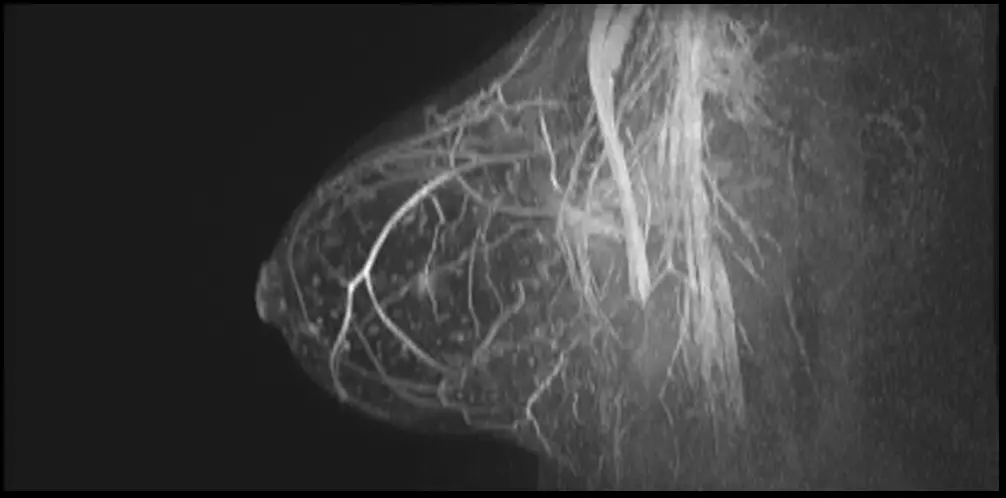

What is Breast MRI?

Breast MRI provides detailed images of internal and soft tissue structures of the breast, which enables a range of diagnostic procedures including assessment of implants, high risk screening and more accurate staging and treatment planning.